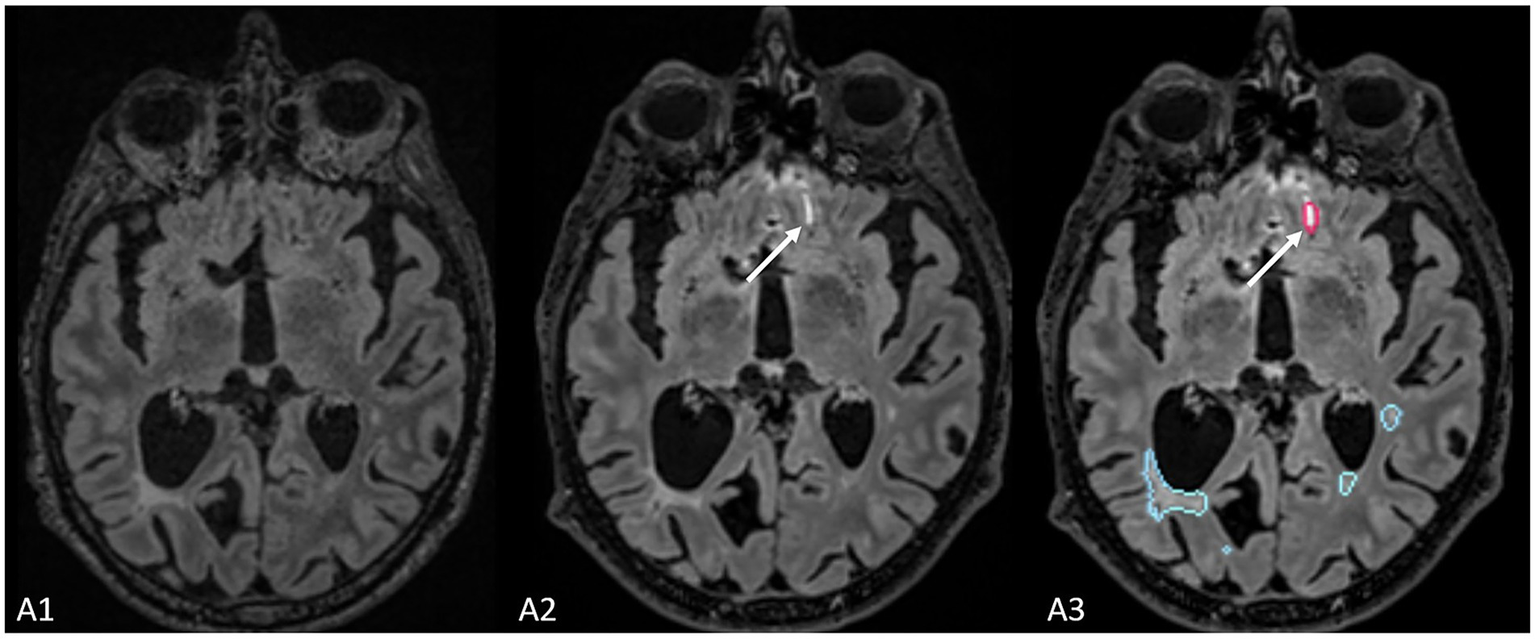

In practical terms, Jazz® enables radiologists to directly compare prior and follow-up scans at the same anatomical location, allowing instantaneous toggling between time points with a single click (mouse or keyboard shortcut). This synchronized display helps the reader identify subtle signal changes. In addition, the software provides a “lesion locking” option: once a lesion is selected, the tool automatically tracks its anatomical location across different time points, ensuring consistent assessment of potential lesion evolution (Figure 1).

Figure 1. The figure represents the reading interface in Jazz® software. It allows a comparison of previous and new MRI FLAIR images of a patient with MS. The reader can easily switch from previous to new image, and vice versa, just by mouse clicking or using a keyboard shortcut (A), while there is as well lesion locking option (B) when the software automatically detects lesion’s anatomical location.